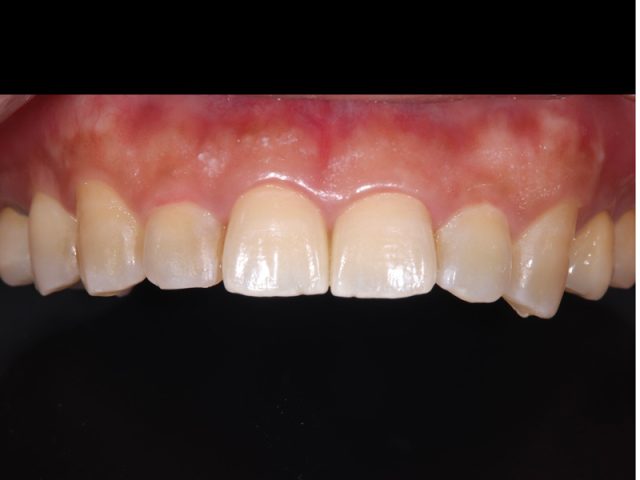

| 診断名 | ラミネートベニア(2本) |

|---|---|

| 年齢・性別 | 30代・男性 |

| 治療期間・回数 | 2週間~3週間/2回 |

| 治療方法 | ラミネートべニアで審美修復 |

| 費用 | 1歯 132,000(税込み) |

| デメリット・注意点 | 保険が適用できないため自費診療になる。 セラミックスインレー・クラウンに強い力がかかると割れてしまう恐れがあるため、歯ぎしりや食いしばりが癖になっている患者様にはおすすめできない場合がある |